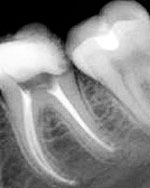

Рентгенологические снимки хорошо запломбированных корневых каналов.